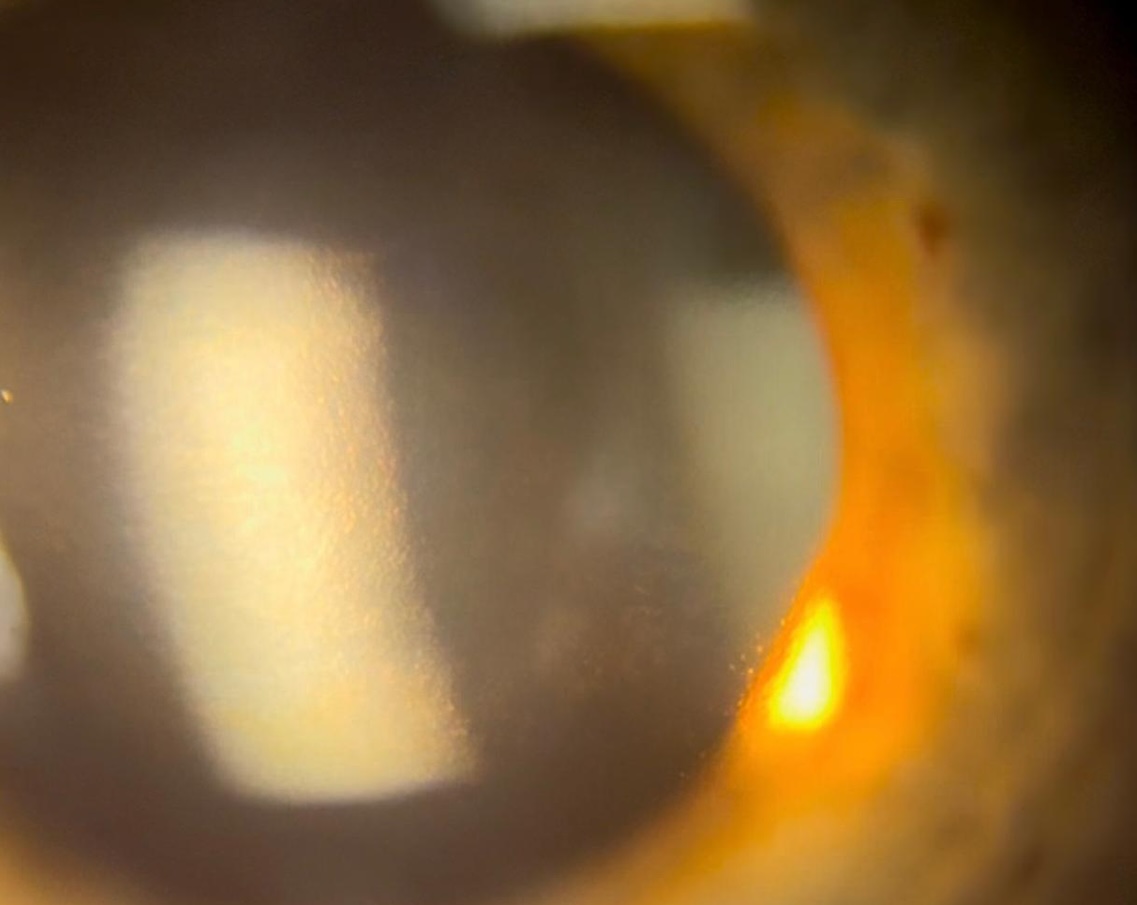

Have an ability to effectively assess the corneal endothelium’s health. Understand, and communicate to patients, the importa… [14588 chars]